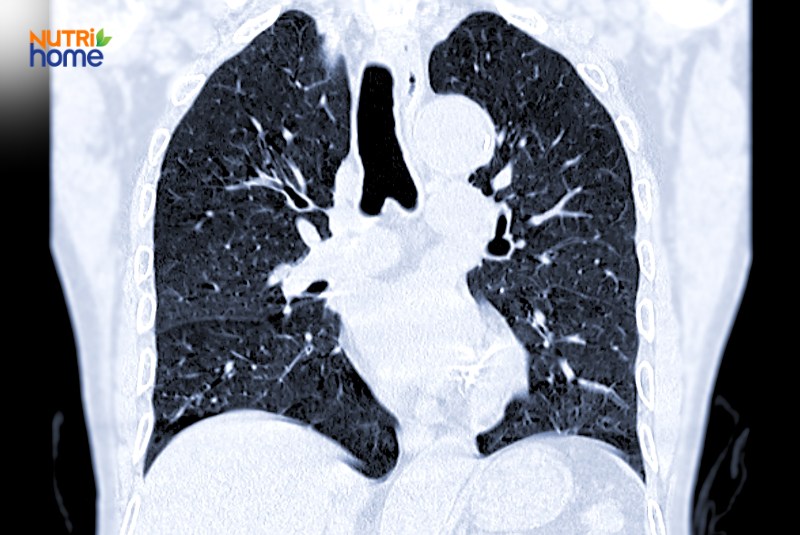

Khi nhận thấy các dấu hiệu này kéo dài hơn 2 tuần hoặc tiến triển nặng dần theo thời gian, bạn nên đến bệnh viện để được bác sĩ khám và làm các xét nghiệm chuyên sâu như chụp X-quang, chụp CT hoặc sinh thiết để chẩn đoán bệnh chính xác hơn.

Ảnh chụp CT phổi có thể giúp tầm soát bệnh ung thư phổi